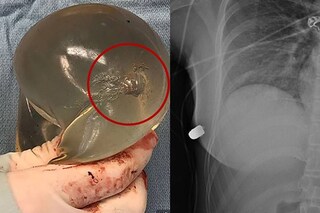

യുവതി ധരിച്ചിരുന്ന കൃത്രിമ സ്തനമാണ് ജീവൻ രക്ഷിച്ചതെന്ന് ഡോക്ടർ പറഞ്ഞു. സിലിക്കോൺ സ്തനത്തിന് വെടിയുണ്ടയേറ്റ് കേടുപാട് പറ്റിയ ചിത്രവും എക്സ്റേ ചിത്രവും പുറത്തുവിട്ടിട്ടുണ്ട്. ശസ്ത്രക്രിയയിലൂടെ ശരീരത്തിൽ തളച്ച വെടിയുണ്ട നീക്കി.

സിലിക്കോൺ സ്തനം വെടിയുണ്ടയുടെ ദിശ തെറ്റിക്കുന്നത് ഇതാദ്യ സംഭവമാണെന്ന് റിപ്പോർട്ടുകൾ പറയുന്നു. എന്നാൽ ഇത്തരത്തിൽ നാലു സംഭവം റിപ്പോർട്ട് ചെയ്തിട്ടുണ്ടെന്നാണ് വിദഗ്ധർ പറയുന്നത്. ഇതിൽ രണ്ട് സംഭവത്തിൽ സിലിക്കോൺ സ്തനം ജീവൻ രക്ഷിച്ചു. എന്നാൽ കേസുകളിലെല്ലാം വെടിയുണ്ട വേഗത കുറഞ്ഞ് ശരീരത്തിൽ തളയ്ക്കുകയായിരുന്നു. എന്നാൽ ദിശക്ക് കാര്യമായ മാറ്റം സംഭവിച്ചതുമില്ല.